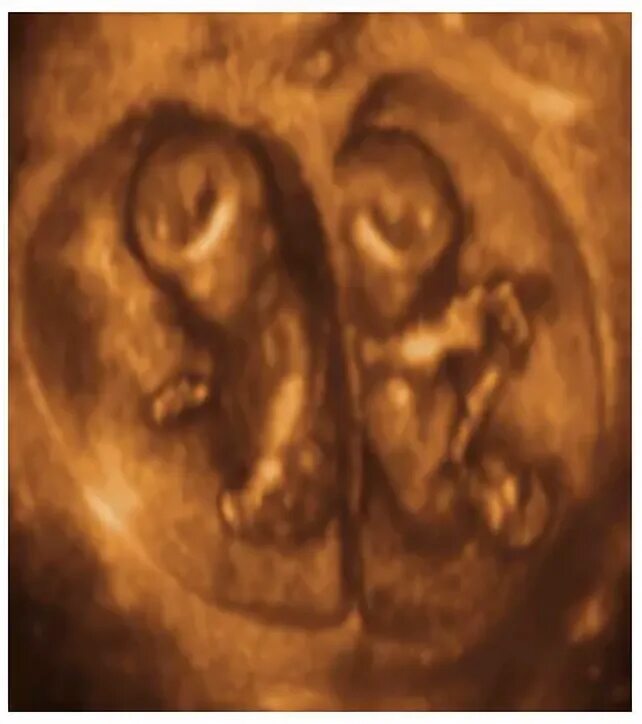

Эмбрион близнецов